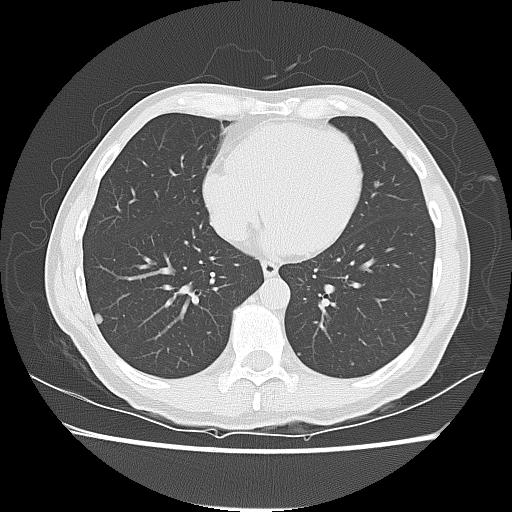

CT Chest / abdomen

Pulmonary metastasis

Metastasis

Mettman et al, Cancer Med 2023

- Retrospective RV of 219 osteosarcoma patients who relapsed with a single pulmonary nodule

- 94.9% achieved successful resection of nodule

- 5y survival post complete resection was 51%, compared to 0% if incomplete